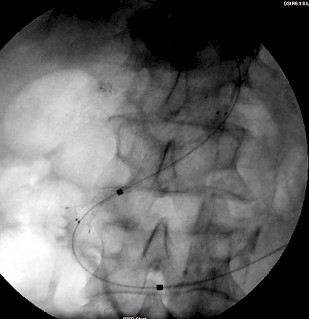

Falls nur der ableitende Gallengang (DHC) stenosiert und versorgt werden muss, kann dieser über den Zugangsweg der PTC/PTCD mittels eines selbstexpandierbaren Stent dauerhaft versorgt werden. Liegt dagegen ein (tumorös bedingter) Verschluss nicht nur des DHC, sondern auch der beiden Hepaticusäste vor (und damit ein Problem des Gallenabfluß aus beiden Leberlappen) sollte eine beidseitige PTC/PTCD erfolgen. Anschließend sollte mittels zweier (parallel über beide Gallengänge bis in den DHC vorgeschobener) Stents eine "Rekonstruktion" der Hepatikusgabel und Schienung des gemeinsamen DHC versucht werden. Ein alleiniges Stenten nur des einen Hepaticusastes (meist von rechts, da der rechte Leberlappen größer als der linke ist) kommt nur in Frage, wenn das erwartete Überleben des Patienten sehr kurz und die linke Leber sehr klein ist. Von beidseits eingebrachte Stents verbessern das Überleben gegenüber nur einem einseitigen Stent

Fallbeispiel:

Patient mit Pankreaskopf-Ca, Leber- und Lungenmetastasen und Tumorverschluß des Gallengangs: